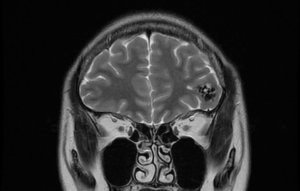

两位分别是16岁的少年和56岁的男士,在没有任何征状时做了详尽的脑及脑血管结构检查,3D三维立体磁力共振脑血管造影显示两人的大脑都有先天性的脑血管动静脉畸形血管瘤,在血管外科医生建议下,经过一段时间的观察和保守治疗,其后利用了微创脑血管导管堵塞手术、加上放射治疗,畸形血管瘤得到了有效根治,病人与生俱来的大脑计时炸弹得以拆除,消除了他们将来出血性中风的风险。

3D 三维立体脑血管造影显示,左边大脑有先天性的脑血管动静脉畸形 (AVM)。